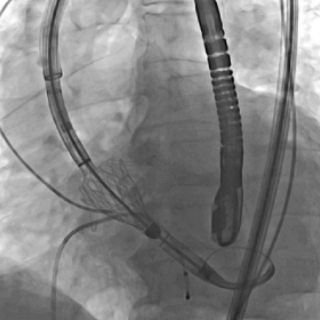

瓣膜实现完美定位与精准释放

瓣膜释放后造影检查瓣膜位置,功能、形态良好,未见明显反流及瓣周漏